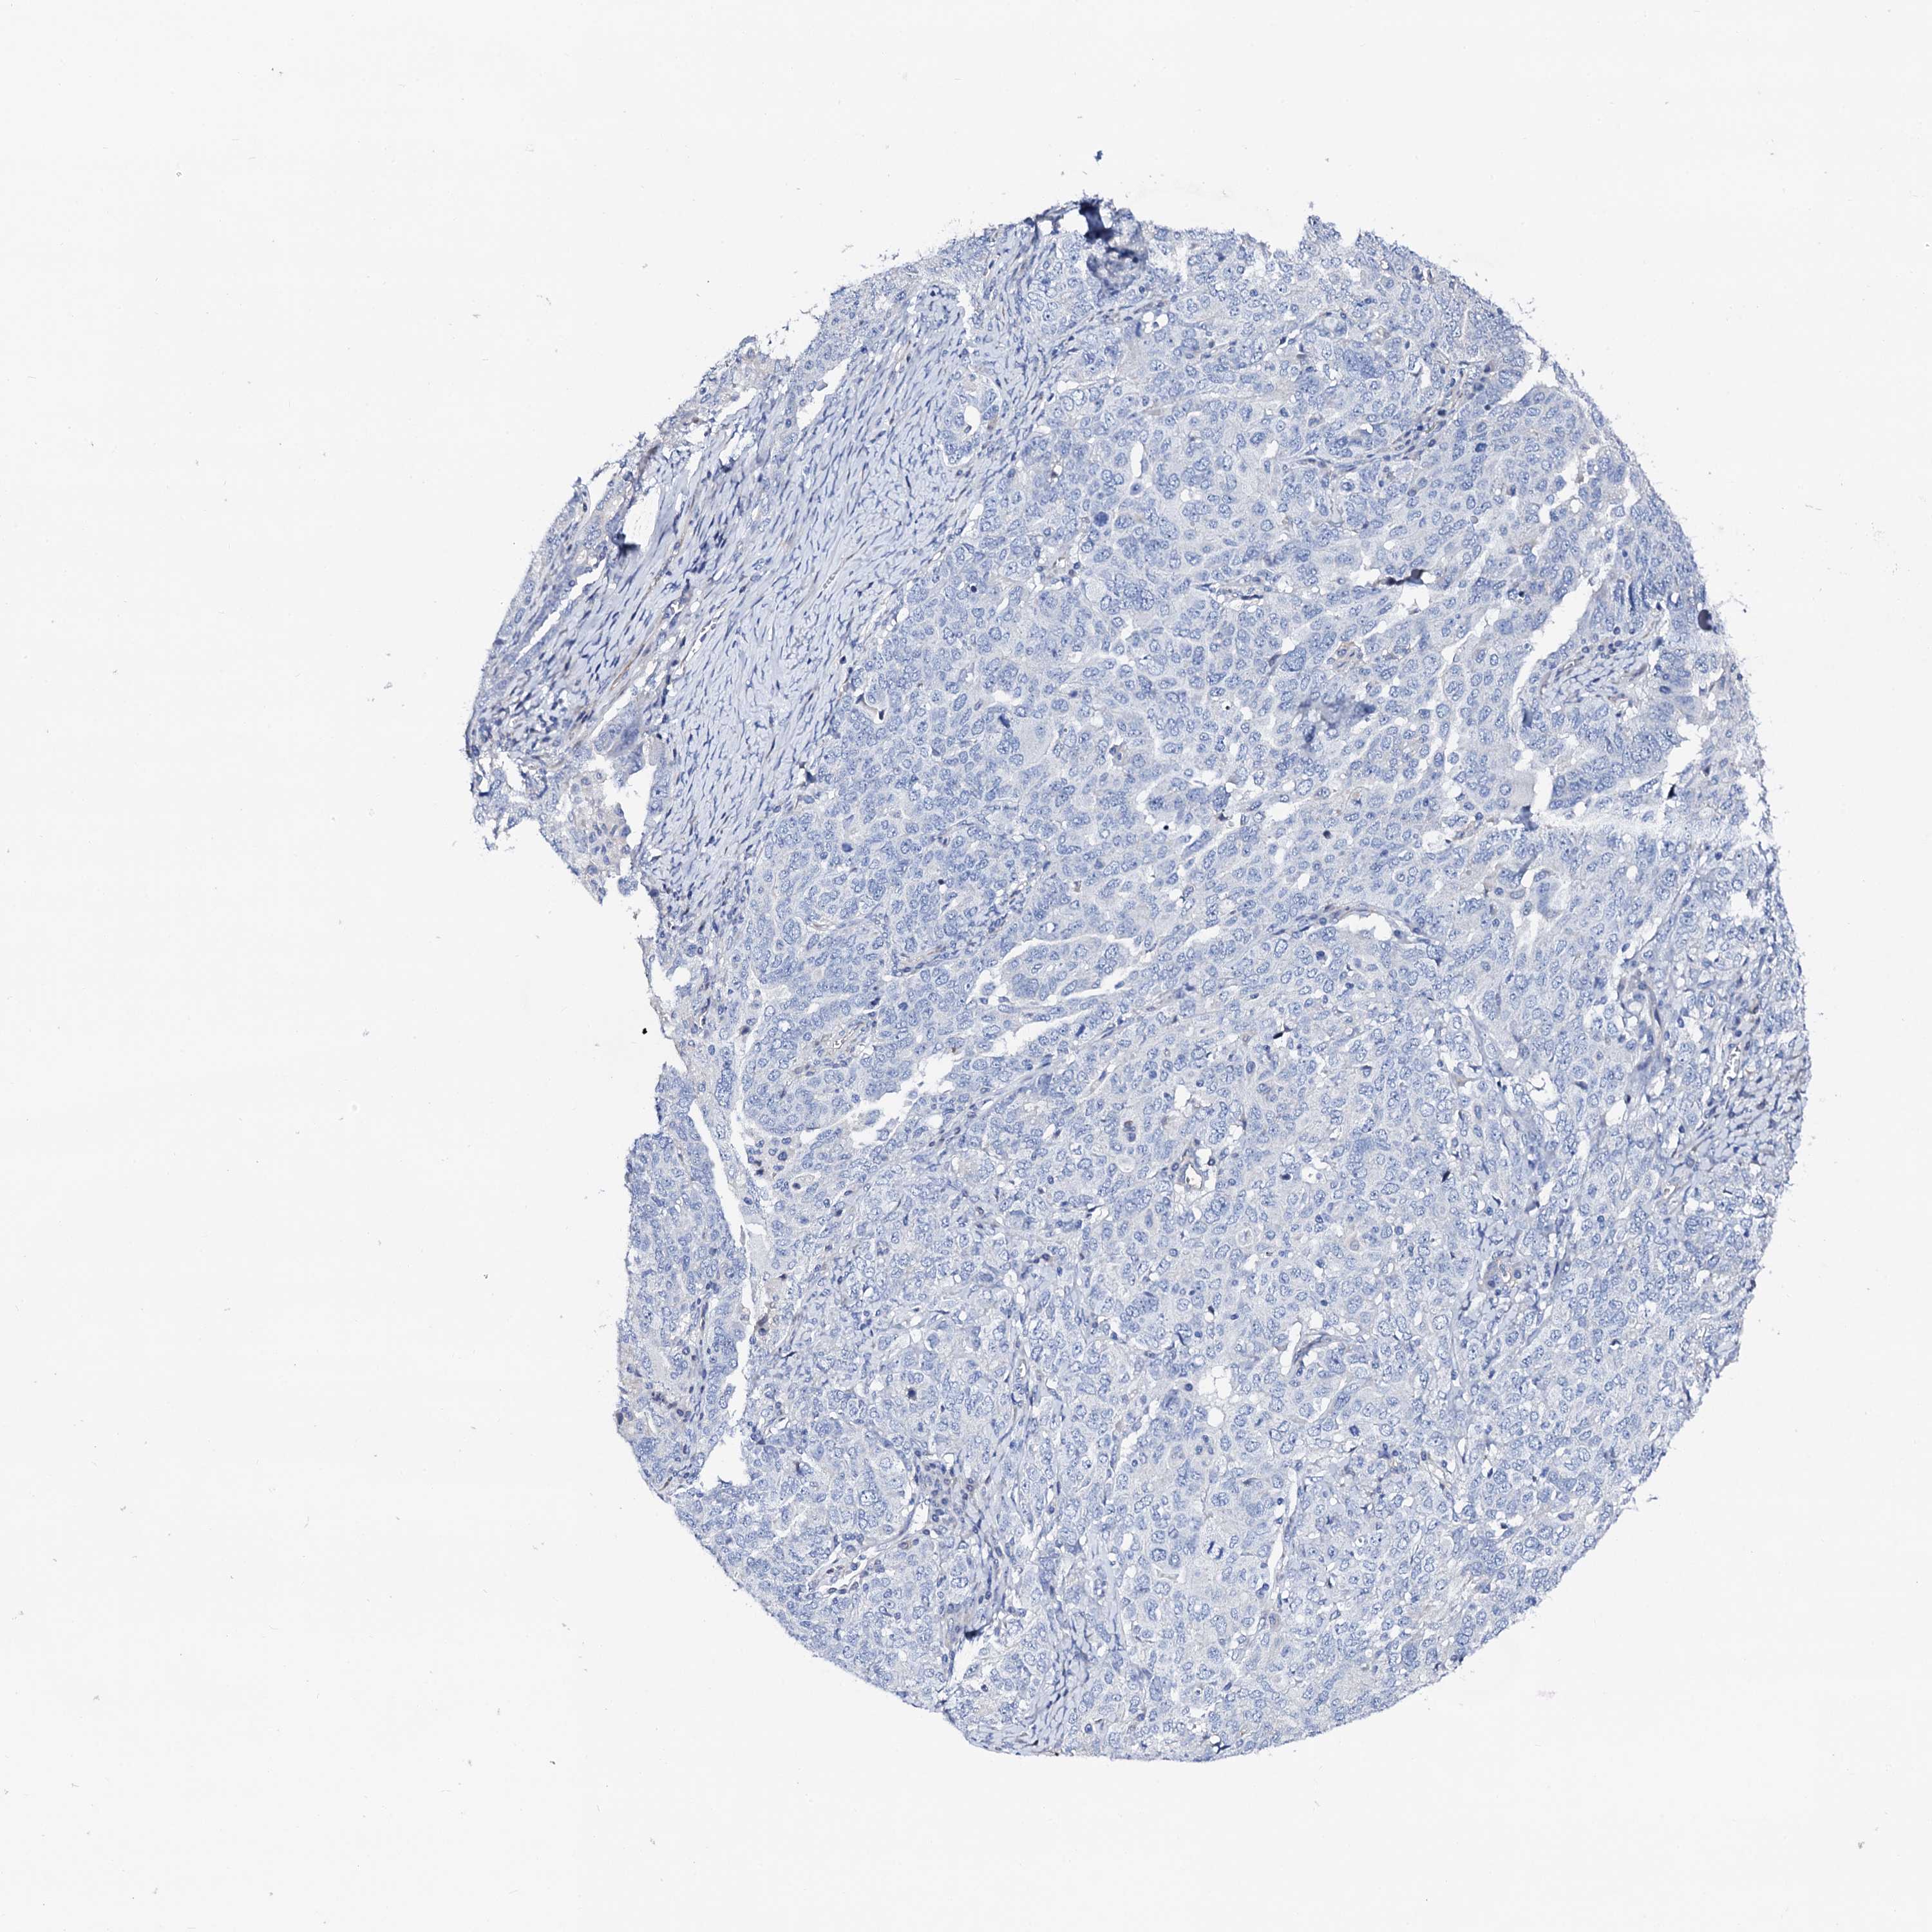

OVARIAN CANCER - Protein expressioni

A mouse-over function shows sample information and annotation data. Click on an image to view it in a full screen mode. Samples can be filtered based on level of antibody staining by selecting one or several of the following categories: high, medium, low and not detected. The assay and annotation is described here.

Note that samples used for immunohistochemistry by the Human Protein Atlas do not correspond to samples in the TCGA dataset.

Antibody stainingi

Antibody staining in the annotated cell types in the current human tissue is reported as not detected, low, medium, or high, based on conventional immunohistochemistry profiling in selected tissues. This score is based on the combination of the staining intensity and fraction of stained cells.

Each image is clickable and will lead to virtual microscopy that enables deeper exploration of all samples and also displays staining intensity scores, fraction scores and subcellular localization as well as patient and tissue information for each sample.

Antibody HPA038226

Antibody HPA058226

Cystadenocarcinoma, serous, NOS

Carcinoma, endometroid

Cystadenocarcinoma, mucinous, NOS

Carcinoma, NOS